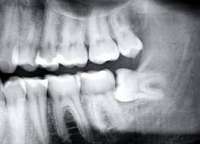

Доброе утро, анон-стоматолог. Помоги советом, пожалуйста.Прошлым летом сделал КТ, на левой нижней шестерке снимок показывает небольшое (1-2 мм) потемнение под тем местом, где к ней примыкает семерка (пик 1), глазами ничего не видно (там семерка примыкает очень плотно, флосс проходит, а швейная нитка - уже нет). Через пару месяцев сделал еще КТ этого места (пик 2), область на снимке вроде бы уменьшилась. Показал снимок стоматологу, он сказал, что это хуйня, и ничего там нет.Два месяца назад снова сделал КТ, темная область увеличилась раза в полтора (пик 3). Стоматолог посмотрел КТ и сам зуб, и опять говорит, что нихуя там нет, что кариес бы просвечивал через эмаль иначе. Визуально тоже ничего не изменилось.За этот год ничего не болело, иногда бывает слегка повышенная чувствительность примерно в этой зоне (но не сильнее, чем у нескольких других мест, где по КТ все нормально). Еще был период неприятного запаха изо рта около месяца, но вполне возможно, что он был из пищевода. Зубы чищу ежедневно, флосс, ирригатор, все дела.Летом я показывал еще скрины последней КТ в проекциях другому стоматологу (у нее нет ридера КТ), она сказала, что похоже на кариес, но она из-за семерки не может подобраться туда аккуратно, и посоветовала найти стоматолога с микроскопом, либо поставить брекет и отодвинуть семерку.Так вот, если не сложно, ответь, пожалуйста, на следующие вопросы:1. По-твоему, кариес это или нет? Если непонятно, то можно ли как-то убедиться в этом точно (скажем, при помощи той цветной хуйни, которую намазывают, и она не смывается с проблемных мест)?2. Может ли это быть просто область с низкой минерализацией ткани, которая видна на КТ, но не на просвет? Имеет ли смысл делать реминерализацию? Если да, то использовать фторлак, или достаточно геля с кальцием типа ROCS?3. Если это кариес, то как в подобном случае делают полость при использовании микроскопа? Энивей заходят на жевательную поверхность, или можно сделать все сбоку, со стороны семерки? Будет ли прочность и долговечность пломбы, заходящей через угол на жевательную поверхность, ниже, чем у обычной?4. Имеет ли на твой взгляд смысл ставить брекет и двигать семерку, чтобы увеличить щель между ними?5. Как бы ты решал проблему на моем месте?Очень рад буду любому совету, меня чрезвычайно напрягает эта ситуация.